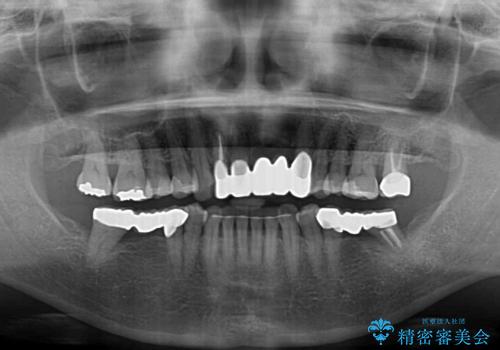

- 前歯の歯肉の腫れを気にして来院された患者様です。

前歯のみならず、奥歯の銀歯や下顎前歯のデコボコなど、色々と気になる部分を治したいとのことでした。

前歯は抜歯が必要であったので、抜歯を行い、その後歯肉移植をおこなった上でオールセラミックブリッジによる補綴治療を行うこととしました。

下顎と上顎臼歯部については矯正治療を行い、奥歯の欠損部位はオールセラミックブリッジを、その他の銀歯はセラミックインレーなどにより治療を行うこととしました。